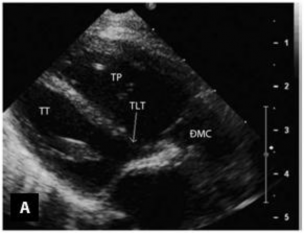

Siêu âm tim thường được bắt đầu với mặt cắt dưới ức giúp đánh giá vị trí và tương quan tạng - nhĩ, kèm theo đó là tình trạng kết nối của hệ thống tĩnh mạch trở về tim và hệ thống tĩnh mạch phổi với mặt cắt dưới sườn (Hình 1.12). Mặt cắt này còn thường được dùng để xác định vị trí và kích thước của vách phễu, độ dày của nếp gấp thất-phễu hai bên. Tiếp đó với mặt cắt bốn buồng dưới sườn cho phép đánh giá mặt sau của vách liên thất và các van nhĩ thất. Khi dịch chuyển đầu dò siêu âm chếch theo chiều kim đồng hồ, đường ra của thất trái và mối liên quan giữa các đại động mạch sẽ được đánh giá, đặc biệt là khoảng cách từ bờ dưới của lỗ TLT tới van ĐMC nhằm xác định chiều dài của đường hầm trong tâm thất cần tái tạo [11],[59].

Hình 1.12: Mặt cắt dưới sườn trục dọc trong chẩn đoán TPHĐR. (A) Hình ảnh của TPHĐR thể Fallot. (B) Hình ảnh siêu âm cho thấy TPHĐR thể TLT kèm theo thương tổn thất phải hai buồng [53]